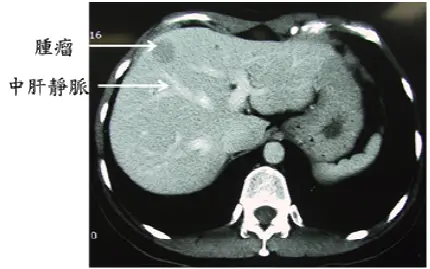

下圖是一位肝癌病人的電腦斷層攝影,根據 Couinaud 等所提出,依照門脈分枝的肝臟解剖學分葉,則腫瘤位於肝臟的那一個小葉?

圖片為腹部橫斷面 CT(軸位),可見:

- 右側(解剖右肝):體積較大,密度均勻

- 左側(解剖左肝):可見一個密度略高或強化的病灶(腫瘤),圖中以「腫瘤」箭頭標記

- 中肝靜脈(middle hepatic vein):圖中以「中肝靜脈」箭頭標記,為一線狀低密度血管影,位於腫瘤的右側(即腫瘤在中肝靜脈的左側)

- 腫瘤位置:位於中肝靜脈左側、鐮狀韌帶/臍靜脈裂(umbilical fissure)右側,即解剖左肝的內側段

根據此解剖位置,腫瘤恰好落在 Couinaud 第 IV 葉(Segment IV) 的範圍內。